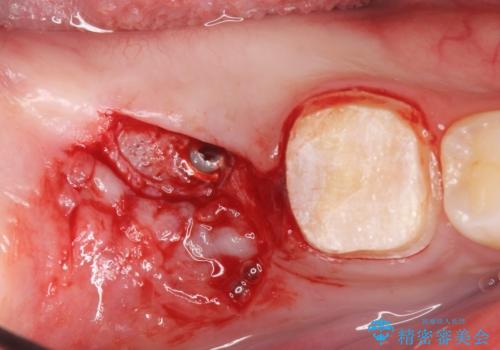

右下の被せ物を外し虫歯を除去したところ虫歯が深く保存が難しい状態だったので抜歯を行いました。

抜歯したところは抜歯後骨の治癒を待ち、CTを撮影しインプラント治療ができる事(骨の厚みなど)確認し治療を行いました。

- 外科手術のため、術後に出血、痛みや腫れ、違和感を伴います